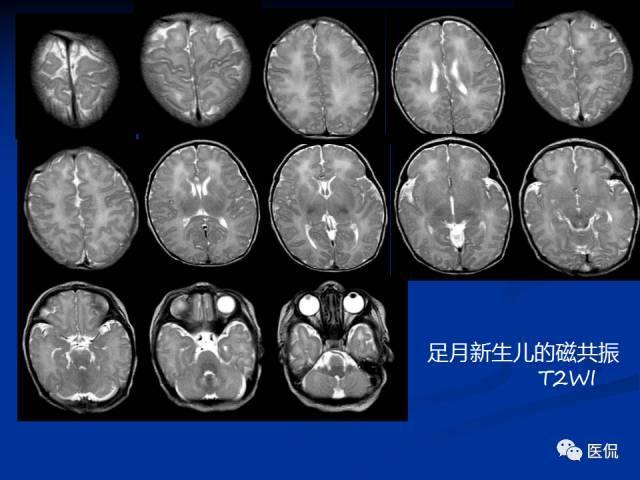

- 磁共振成像(MRI): 这是评估脑损伤程度的“金标准”,它能更清晰地显示大脑不同区域的损伤情况,对于轻度HIE,MRI通常显示正常或仅有非常局灶、轻微的异常。